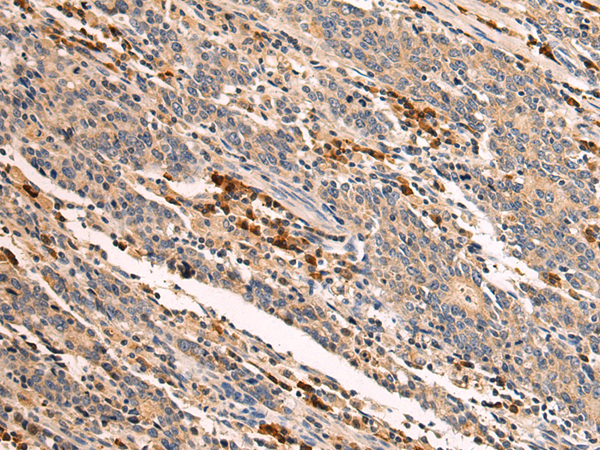

分类: 科研抗体货号: P07776别名: CT15; FTNB; PH30; CRYN1; CRYN2; PH-30b; PH30-beta应用: IHC反应种属: Human